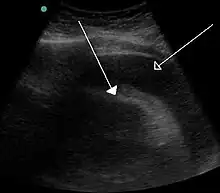

Echocardiogram (ultrasound): when pericardial effusion is suspected, echocardiography usually confirms the diagnosis and allows assessment of the size, location and signs of hemodynamic instability.[4] A transthoracic echocardiogram (TTE) is usually sufficient to evaluate pericardial effusion and it may also help distinguish pericardial effusion from pleural effusion and MI. Most pericardial effusions appear as an anechoic area (black or without an echo) between the visceral and the parietal membrane.[1] Complex or malignant effusions are more heterogeneous in appearance, meaning they may have variations in echo on ultrasound.[5] TTE can also differentiate pericardial effusion based on the size. Although it's difficult to define size classifications because they vary with institutions, most commonly they are as follows: small <10, moderate 10–20, large >20.[5] An echocardiogram is urgently needed for evaluation when there is concern for hemodynamic compromise, a rapidly developing effusion or history of recent cardiac surgery/procedures.[1]

Cardiac CT and MRI scans: cross-sectional imaging with computed tomography (CT) can help localize and quantify the effusion, especially in a loculated effusion (an effusion contained to one area).[12] CT imaging also helps assess for pericardial pathology (pericardial thickening, constrictive pericarditis, malignancy-associated pericarditis).[1] Whereas cardiac MRI is reserved for patients with poor echocardiogram findings and for assessing pericardial inflammation, especially for patients with continued inflammation despite treatment.[5] CT and MRI imaging can also be used for continued follow up on patients.